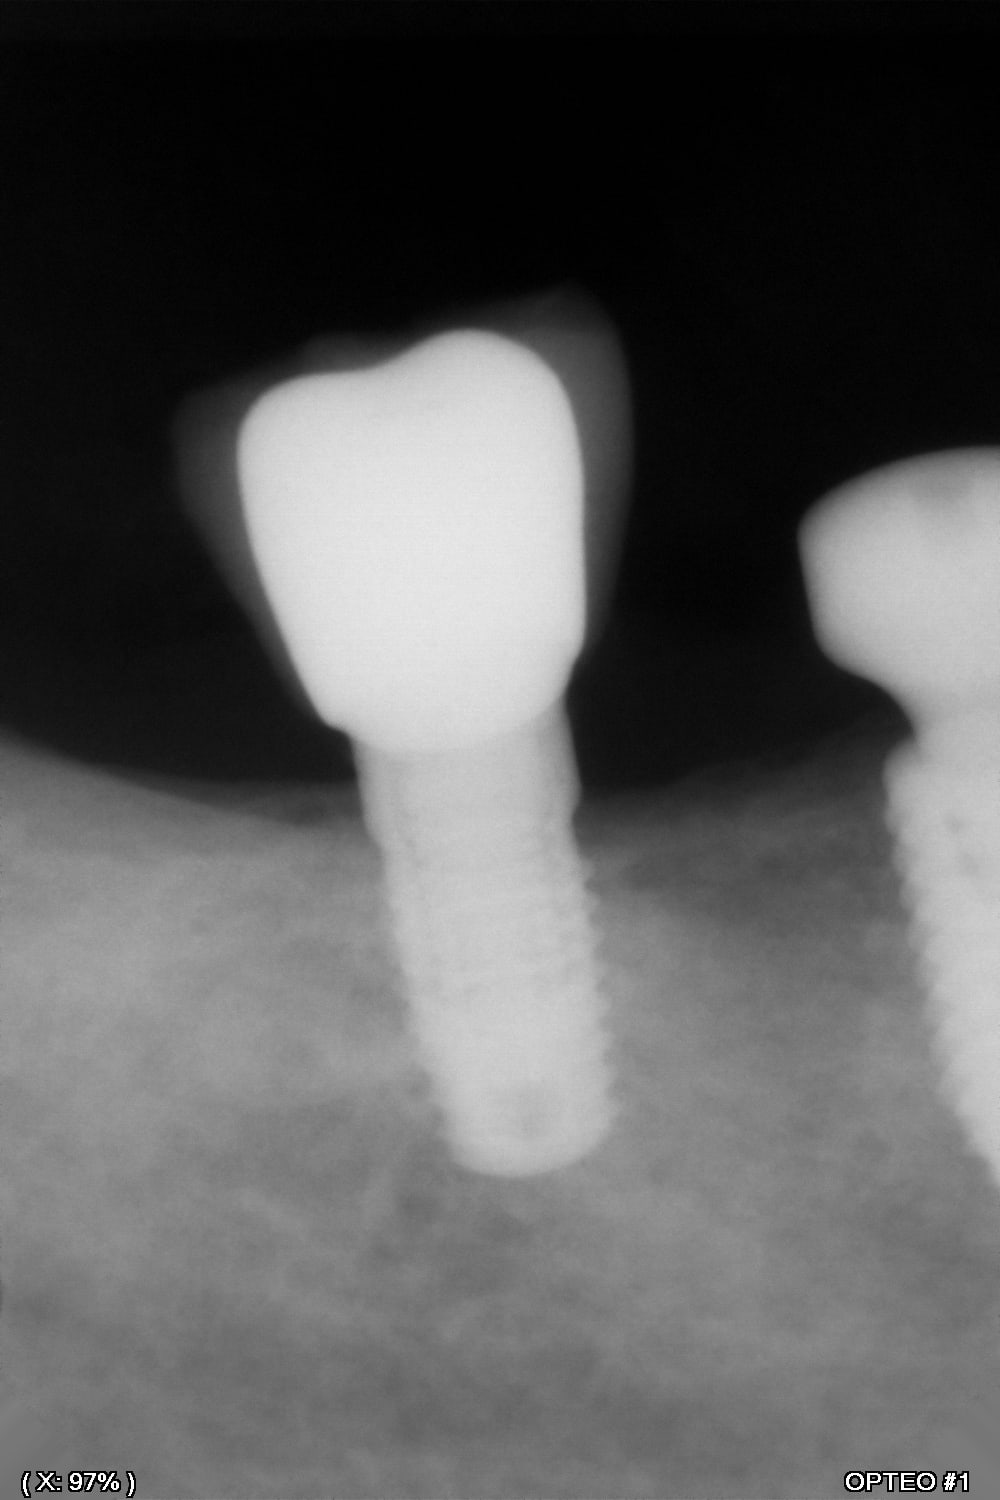

D'après vous, quelle est la marque de cet implant...?

CAMLOG?

camlog screw line je dirais